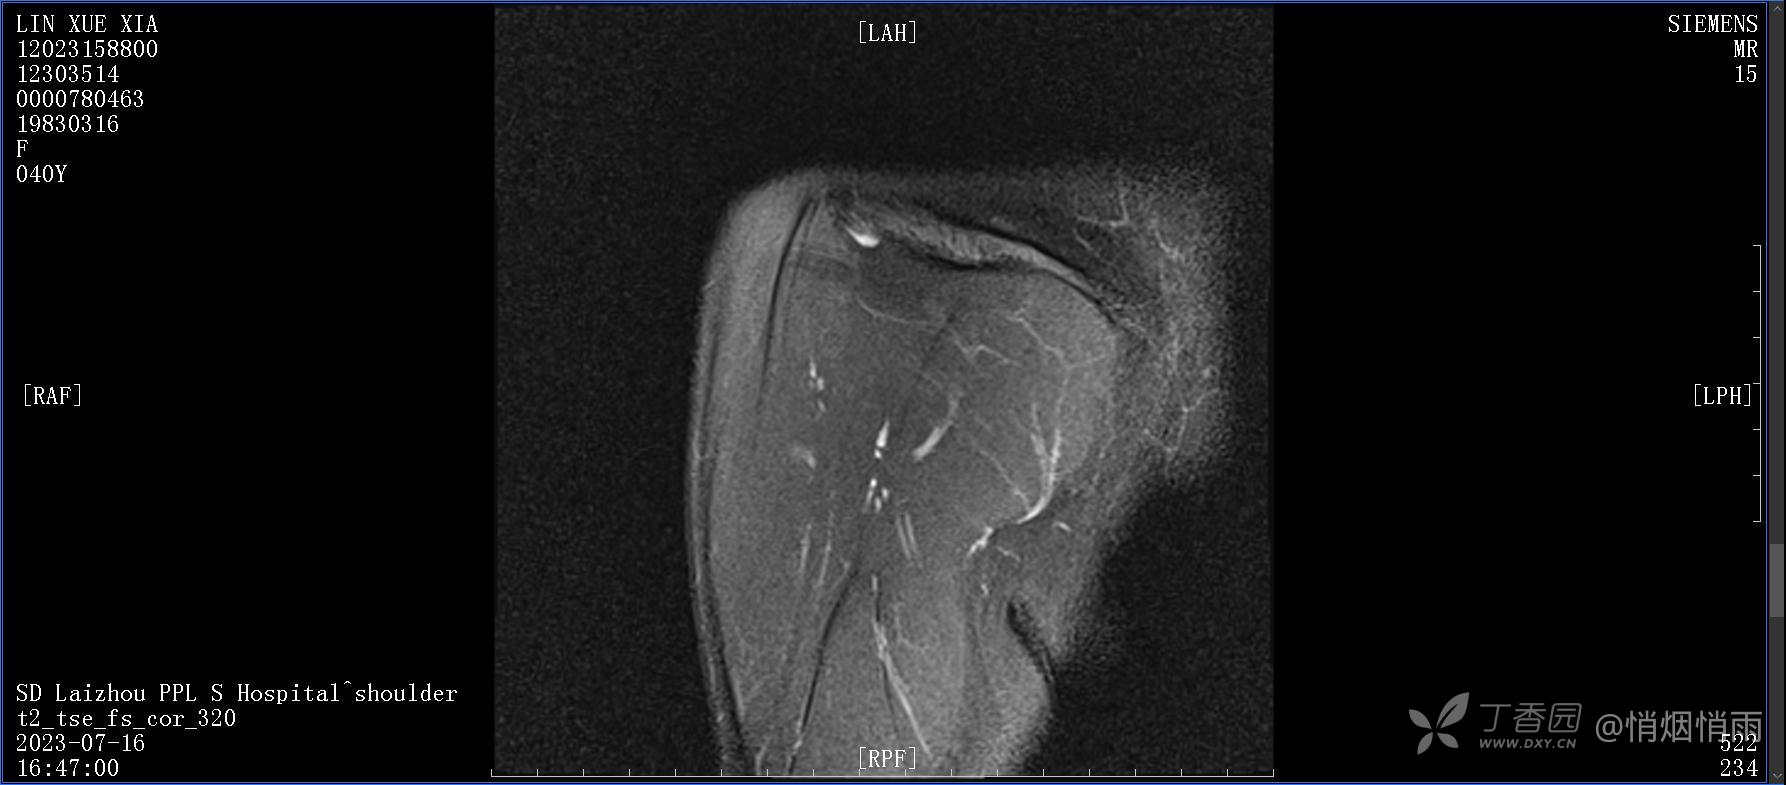

查体:右肩关节局部轻度肿胀,肩胛区压痛明显,痛处不固定,肩关节痛性活动受限,jobe test(+),lift -off test(+),中指、环指感觉较余指减退,余肢端感觉及血运情况可。

目前的诊断,暂时依据辅助检查诊为肩袖损伤,但是患者疼痛的性质和特点,却不是单纯的肩袖损伤所致。考虑过胸廓出口综合征,但是该疾病会出现肩胛区的疼痛吗?(由于考虑到费用的问题,没再进行下一步的检查)带状疱疹会有如此的症状吗?